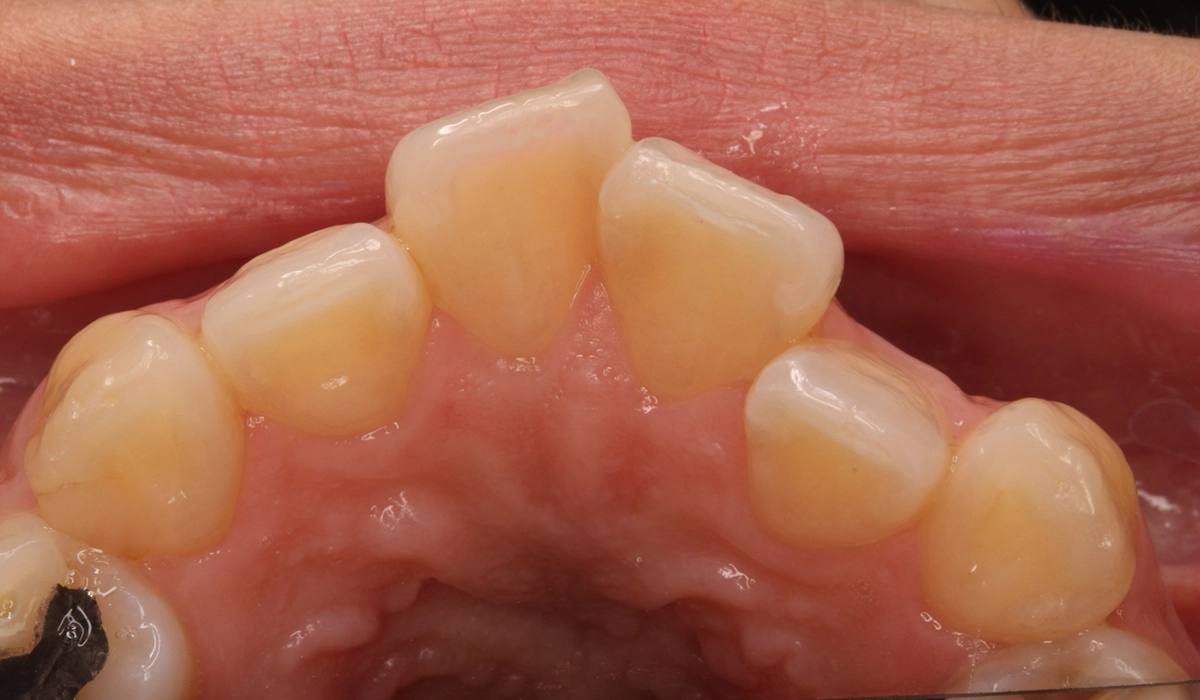

術前:上顎前歯部寄り

術前:下顎前歯部寄り